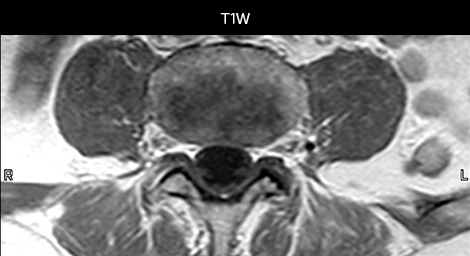

Cervical spine routine exam

This patient presented with headache that was worse with neck flexion and we see a Chiari 1 malformation with low-lying cerebellar tonsils as well as some degenerative cervical thrombolytic change.